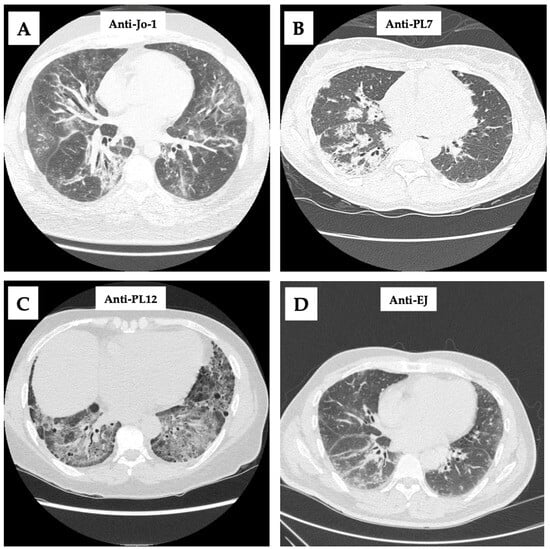

- Anti-Jo-1 (Anti-Histidyl tRNA Synthetase)

- Anti-PL7 (Anti-Threonyl tRNA Synthetase) and Anti-PL12 (Anti-Alanyl tRNA Synthetase)

- Anti-EJ (anti-glycyl tRNA synthetase)

- Waseda, Y.; Johkoh, T.; Egashira, R.; Sumikawa, H.; Saeki, K.; Watanabe, S.; Matsunuma, R.; Takato, H.; Ichikawa, Y.; Hamaguchi, Y.; et al. Antisynthetase syndrome: Pulmonary computed tomography findings of adult patients with antibodies to aminoacyl-tRNA synthetases. Eur. J. Radiol. 2016, 85, 1421–1426. [Google Scholar] [CrossRef]